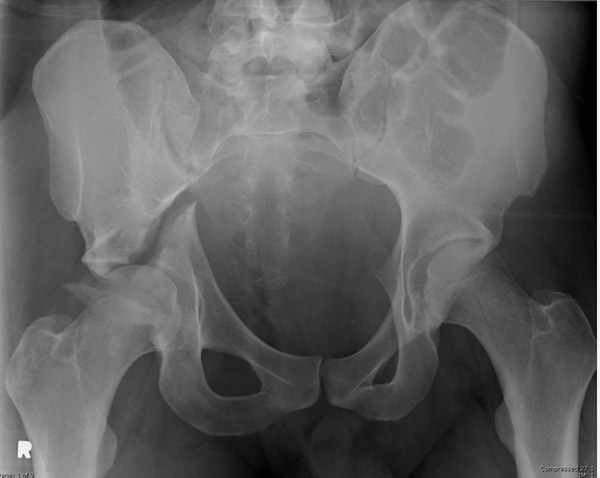

Перелом вертлужной впадины отличается от “переломов таза” не только исследованием, но также тактикой. По классификации Летурнеля расположение линии перелома характерно для поперечного перелома вертлужной впадины, но наличие шурупов в заднем крае (второй снимок) и вывих бедра подтверждают, что здесь сочетание заднего края с поперечным переломом.

Надо сделать снимки Judet и при возможности КТ. А 3Д снимки покажут общий вид, но детали в области суставов дает срезы КТ.

http://www.e-radiography.net/radiology/acetabular%20fractures.pdf

Классификация Летурнеля подсказывает пути доступов, но самым главным в лечении переломов вертлужной впадины является репозиция! При поперечных переломах линия перелома спереди кзади, и доступ в зависимости от смещения должен быть Kocher-Langenbeck или передние: Smith Petersen, Ilioinguinal. Вариант доступа Stoppa тоже подойдет, но это детали...